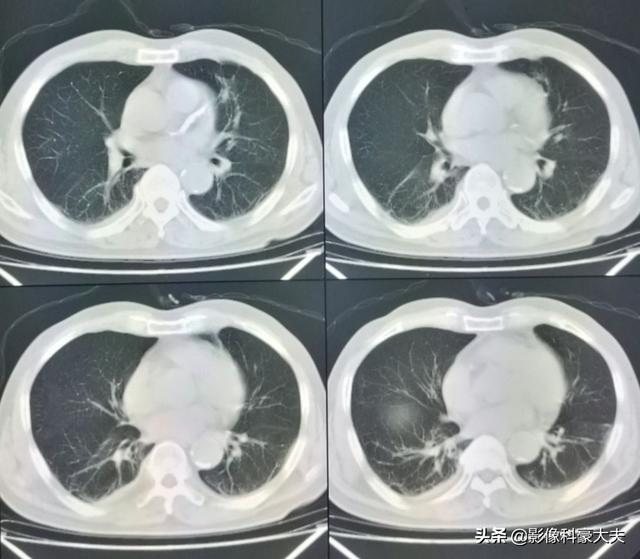

Dieser unregelmäßige Knoten in der linken Lunge ist der Primärherd, der nur 2,6 cm groß ist. Lungenkrebs mit Knochenmetastasen wie diesem ist nicht mehr operabel. Man kann ihm nicht helfen, Lungenkrebs ist zu häufig und einige der frühen Symptome sind atypisch oder sogar symptomlos.Bei etwa 30 % der Lungenkrebse sind Symptome von Metastasen die erste Manifestation, und Metastasen werden zuerst entdeckt, bevor weiterer Lungenkrebs entdeckt wird.

Gerade vor ein paar Tagen nur einen Fall von Lungenkrebs Knochenmetastasen Patienten diagnostiziert, ist sein Symptom langfristige lumbale Rückenschmerzen, haben sie immer gedacht, dass es lumbale Muskelzerrung ist, oder von lumbalen Bandscheibenvorfall leiden, kümmerte sich nicht, wirklich der Schmerz ist ernst, und erschien die Nervensymptome der unteren Gliedmaßen, nur in das Krankenhaus für die Prüfung, gegeben, um seine CT-Untersuchung, festgestellt, dass es offensichtlich Wirbelknochen Zerstörung sind ...... detaillierte Verfolgung der Krankengeschichte, festgestellt, dass der Patient seit langem Hustensymptome hat, so hoch Verdacht auf Lungenkrebs Knochenmetastasen, die Lunge CT-Untersuchung, fand der primäre Fokus ...... eine große Lungenkrebs.

In einem Fall wurde ein 46-jähriger Mann wegen anhaltender Schmerzen im unteren Rückenbereich untersucht. Es wurde vermutet, dass es sich bei den Kreuzschmerzen um einen Bandscheibenvorfall handelte. Es wurde eine Röntgenaufnahme gemacht, die keine Anomalien zeigte. Knochenmetastasen, die eine leichte Knochenzerstörung verursachen, sind auf Röntgenbildern nicht sichtbar, und auch ein Bandscheibenvorfall ist auf Röntgenbildern nicht zu erkennen. Daher dachte ich nicht besonders über die Möglichkeit einer Metastase nach. Eine Woche später, als immer noch keine Besserung eingetreten war, kam er zum CT und stellte fest, dass ein Lendenwirbel angefressen war. Als der bildgebende Arzt ein solches Bild sah, musste er an die Möglichkeit einer Metastase denken und schlug dem Patienten eine CT-Untersuchung des Brustkorbs vor, und tatsächlich fand sich eine Masse in der Lunge, die als Knochenmetastase von Lungenkrebs angesehen wurde, was später von der Pathologie bestätigt wurde.